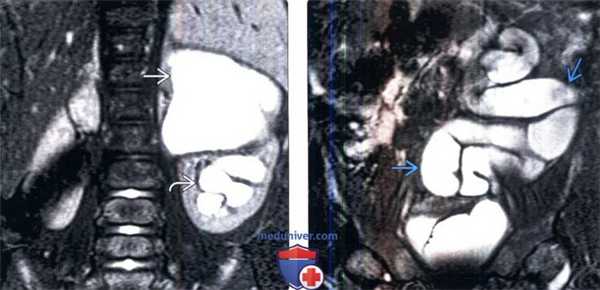

(Левый) На фронтальном Т2 HASTE МР-изображении лучше визуализируется удвоенная левая почка с окклюзированной атрофированной верхней лоханкой. Расширенный извитой мочеточник впадает во влагалище. Мочеточник утолщен в результате инфекционного процесса.

(Правый) На аксиальном Т1 FS снимке с контрастированием визуализируется эктопическое впадение левого верхнего мочеточника во влагалище. Усиление сигнала от стенки мочеточника и окружающих тканей обусловлено развитием инфекции.

(Слева) МРТ, Т2-ВИ, корональный срез: удвоение левой собирательной системы с заметным гидронефрозом верхнего полюса и умеренным гидронефрозом нижнего полюса.

(Справа) МРТ, Т2-ВИ, корональный срез: у этого же пациента отмечается заметное расширение и извитость части эктопического мочеточника верхней лоханки.